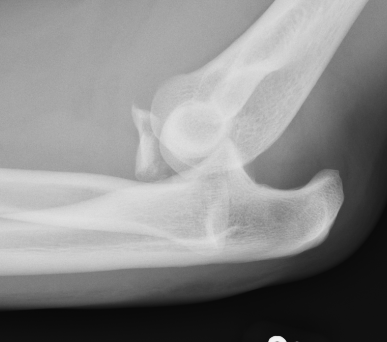

Elbow dislocation with radial head fracture

Management

Critical to elbow stability

Based upon Mason classfication